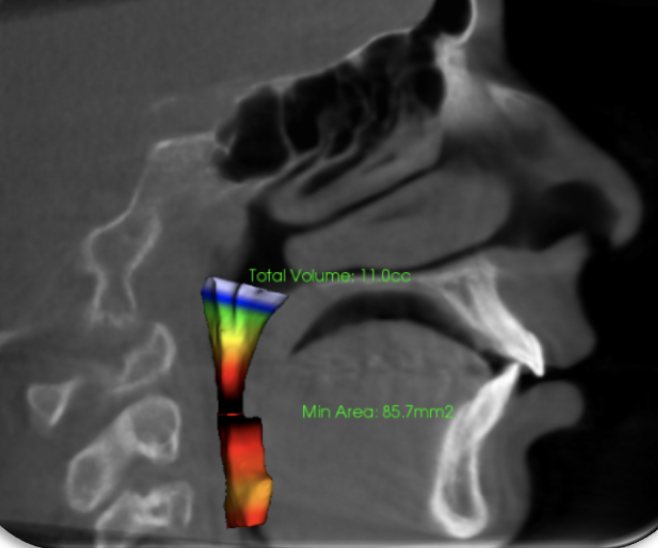

Meet Felix the iCAT! This the name of our 3D X-ray machine. At Buena Vista Orthodontics, we utilize state-of-the-art iCAT 3D imaging technology to provide comprehensive diagnostic capabilities. Nothing hides from us. In 3D, we could capture detailed images of your This advanced cone beam CT teeth, bone, TMJ, airways and much more, giving us a superior diagnostic capabilities.

Why iCAT 3D Imaging? Just look and see for yourself!

The iCAT system visualizes areas that traditional X-rays cannot show, including tooth roots, bone density, airway passages, and TMJ structures. This enhanced imaging enables us to create more accurate treatment plans and identify potential complications early.

With iCAT 3D imaging, we provide faster diagnoses and ensure the most effective treatment approach for your specific needs. The low-radiation technology prioritizes patient safety while delivering exceptional image quality for optimal results.